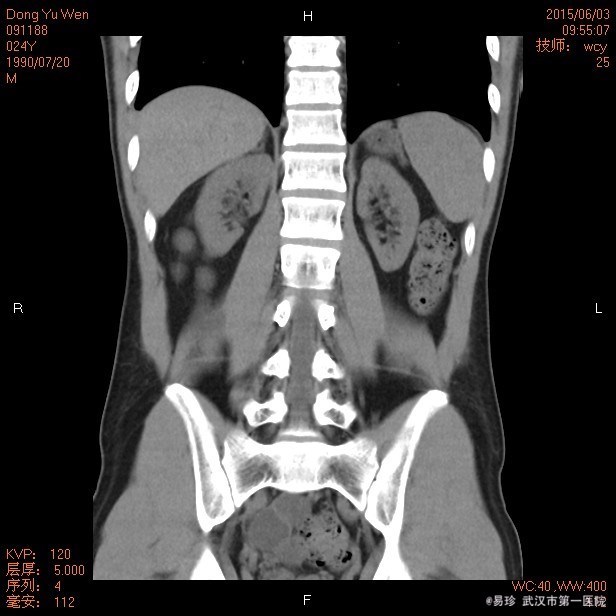

查体:生命体征平稳,听力下降,心肺听诊未见明显异常,腹软、无压痛,双下肢无水肿。 辅查: 泌尿系CT:双肾慢性肾病表现,双肾小结石,右肾轻度积液,右侧输尿管上段扩张,中下段显示不清。